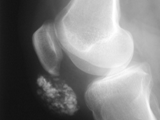

Multiple hereditary exostoses-knee

Multiple hereditary exostoses-knee